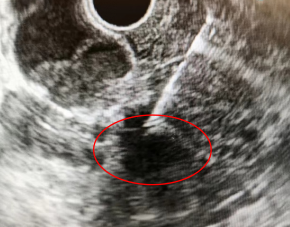

超聲內鏡下顯示的病灶

該患者因“反復發熱及上腹痛1月余”先后就診于我院感染性疾病科及肝膽胰外科,實驗室檢測聯合影像學檢查未能明確診斷。為進一步明確病因,經我院消化內科會診后,建議進一步完善超聲內鏡(EUS)檢查。經EUS檢查后,考慮為膽總管下端占位性病變,伴膽總管截斷、梗阻、炎癥改變。遂進一步通過EUS-FNA獲取占位性病變的組織病理學標本,隨后我院病理科結合組織病理學表現和免疫組織化學染色結果,明確診斷為腺癌,考慮膽管來源。